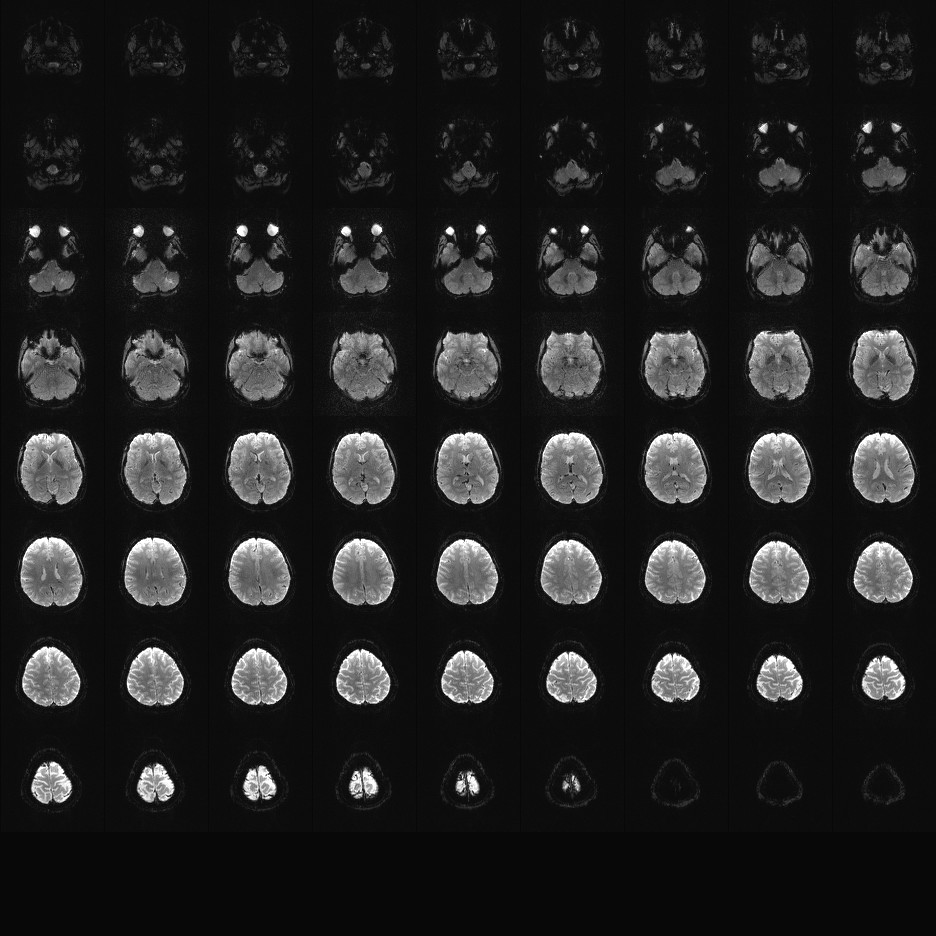

Multi-banded RF pulses can be used to accelerate volume coverage along the slice direction by simultaneously exciting and acquiring multiple slices and subsequently unaliasing them using parallel imaging principles and the spatial information available in multi-channel RF array coils.

This allows for a direct reduction in the volume TR by the number of simultaneously excited slices (i.e., the multiband (MB) factor or the slice acceleration factor).